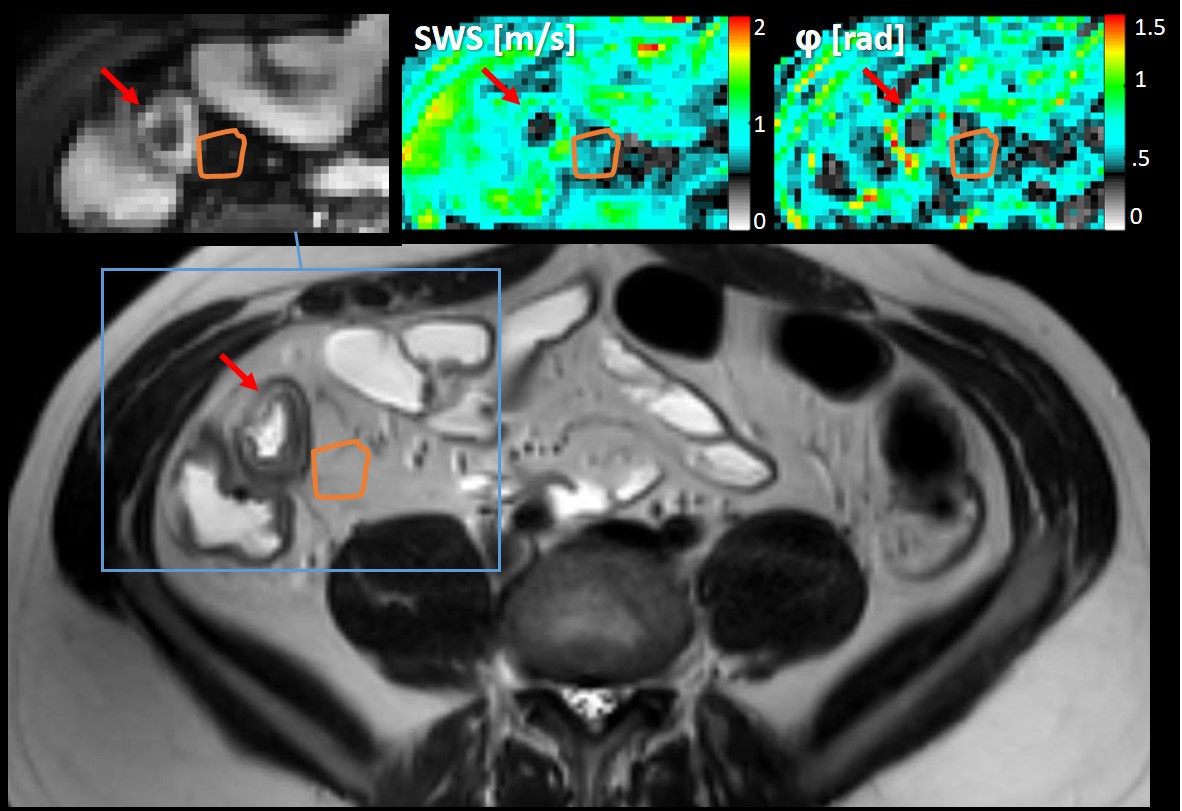

Healthy volunteer repeatability 95%-limits-of-agreement (LoA) were [-0.09, 0.13 m/s ], [-0.09, 0.12 kPa], [-0.10, 0.09 m/s] and [-0.12, 0.13 rad] for the SWS, |G*|, a and φ respectively, see figure 2. MR-Elastography parameters and scores for all patients can be found in figure 1c. Comparison of biomechanical properties with histopathology and fatty wrapping scores are depicted in figure 2 and 3. Shapiro-Wilk test for normality showed a normal distribution for attenuation only. Comparison with healthy volunteers showed no significant difference for the attenuation (mean a=[0.80±.0.21, 0.67±0.07 m/s], p=0.18), whilst the SWS, |G*| and φ did show significant differences (median SWS=[0.76(0.64-1.19), 0.64(0.53-0.74) kPa], |G*|=[0.68(0.65-0.90), 0.58(0.55-0.63) kPa], φ=[0.55(0.49-0.90), 0.45(0.28-0.64) rad], t=3, df=6, p=.02, p<.001, p=.02, respectively), see figure 4. In figure 5 an elastogram of a representative patient with aCD at the ileocecal junction is shown.

Figure 5 Region of interest of affected bowel mesentery in a representative patient with Crohn’s Disease on the T2-weighted images, on top in the inset is the corresponding anatomical MR elastography image with the shear wave speed (SWS) and phase angle (phi) map. Affected mesentery is highlighted in orange and the red arrow shows the affected bowel wall.